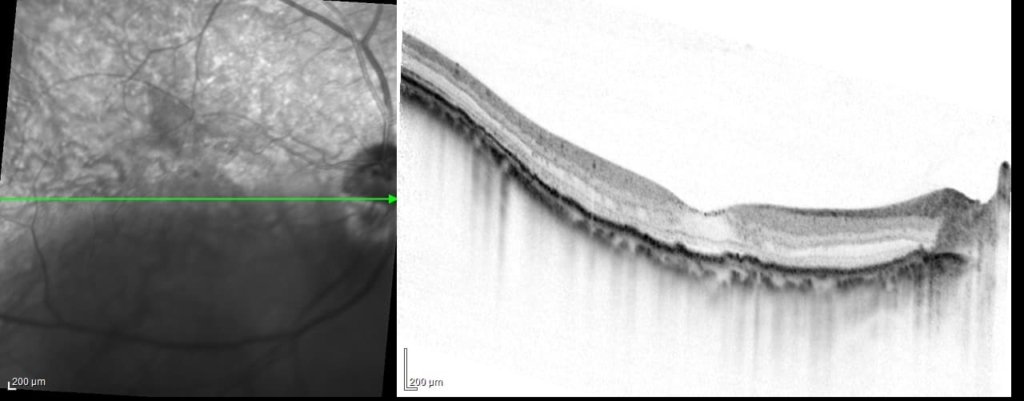

両眼ともに、後部ぶどう腫staphylomaの上縁に一致して乳頭下縁から黄斑を横断するように帯状の網脈絡膜の萎縮巣がみられる。また後部ぶどう腫領域に一致して網膜・脈絡膜が菲薄化しているため、紋理眼底tessel lated fundusがみられる。

後部ぶどう腫の上縁に漿液性網膜剥離(SRD)がみられる。この後部ぶどう腫と正常部の境界付近に脈絡膜新生血管の発生を見ることもあるため、注意が必要。